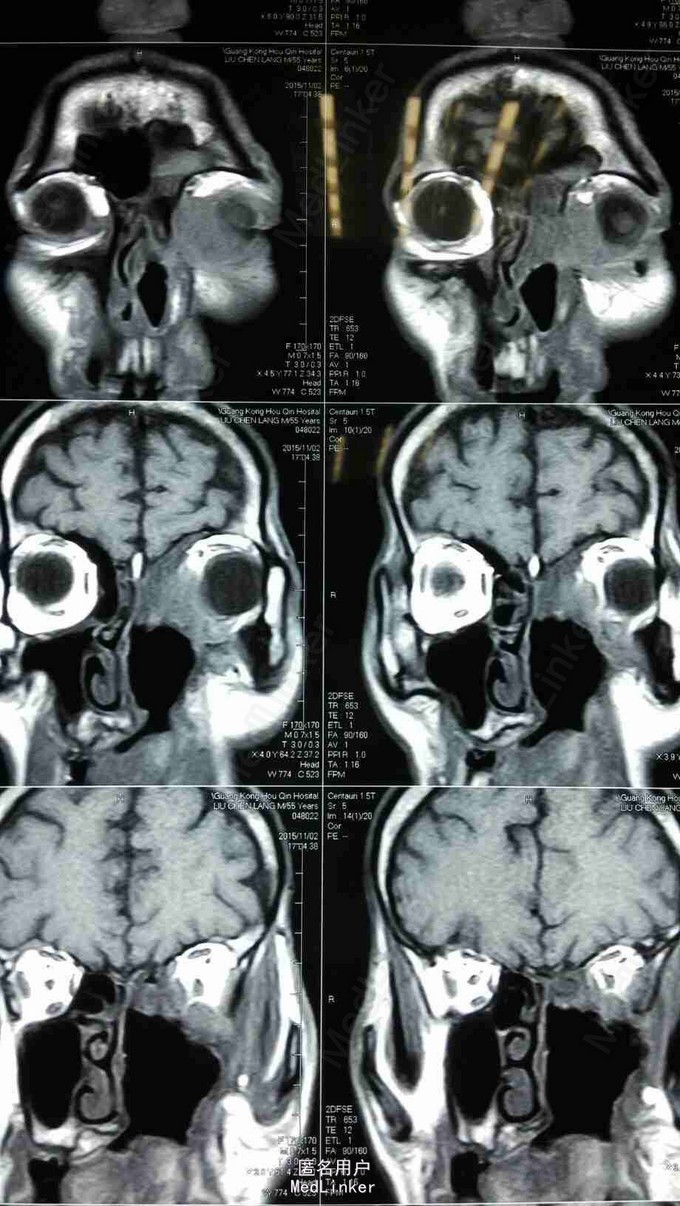

查体:患者神清,消瘦,发音不清,全身浅表淋巴结未见肿大,左眼上睑内侧可见肿物,大小约1*1cm,皮肤红肿,无破溃,质硬,伴压痛,不活动,眼睑闭合不全,睫毛方向正常,眼部可见少量脓性分泌物。 MRI:左侧上颌窦术后改变,左上颌窦顶壁及左眼眶内下方异常信号,考虑肿瘤复发,累及左眶内眦部,前组部分筛窦,内下方肌间隙及上下眼睑内侧份。